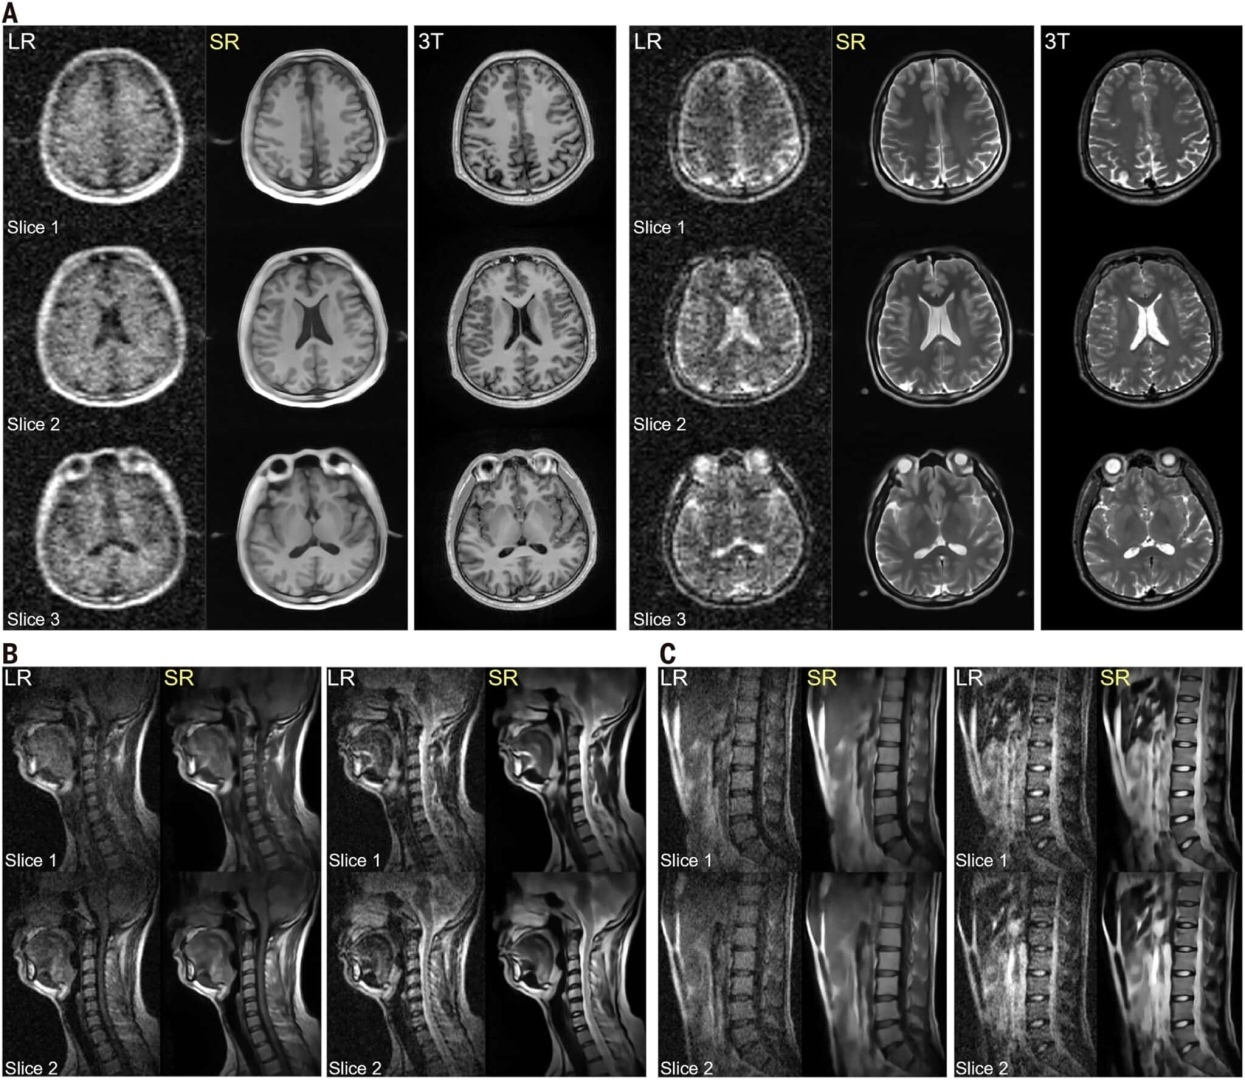

Технологии, делающие аппараты МРТ мобильнее, уже активно разрабатываются. Недавно инженеры из Гонконгского университета успешно протестировали экспериментальный аппарат для МРТ, который работает с магнитным полем мощностью 0,05 тесла, в отличие от стандартных аппаратов, которые работают с полем мощностью один-три тесла. Ученые оптимизировали самые дорогие составляющие сканера и повысили резкость изображений органов с помощью алгоритма глубокого обучения.